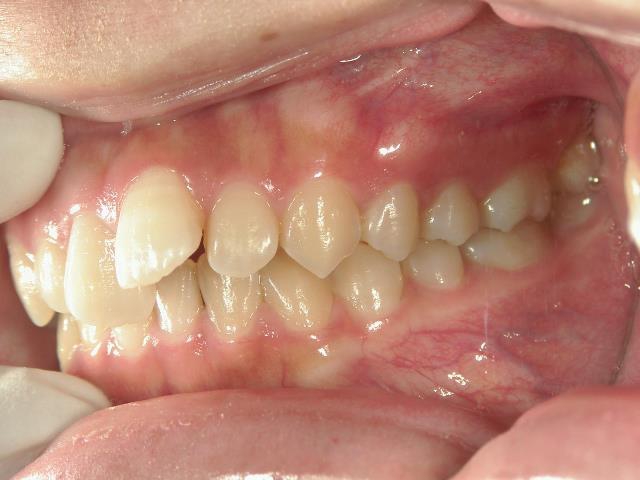

矯正歯科 治療前 右

矯正歯科 治療後 右